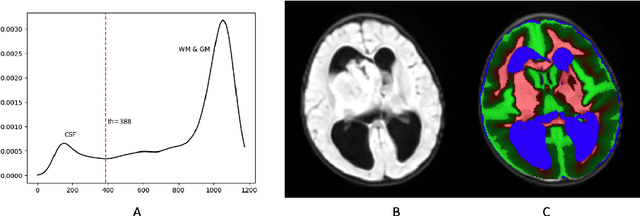

Abstract:Surgical resection is a common procedure in the treatment of pediatric posterior fossa tumors. However, surgical damage is often unavoidable and its association with postoperative complications is not well understood. A reliable localization and measure of cerebellar damage is fundamental to study the relationship between the damaged cerebellar regions and postoperative neurological outcomes. Existing cerebellum normalization methods are not reliable on postoperative scans, therefore current approaches to measure surgical damage rely on manual labelling. In this work, we develop a robust algorithm to automatically detect and measure cerebellum damage due to surgery using postoperative 3D T1 magnetic resonance imaging. In our proposed approach, normal brain tissues are first segmented using a Bayesian algorithm customized for postoperative scans. Next, the cerebellum is isolated by nonlinear registration of a whole brain template to the native space. The isolated cerebellum is then normalized into the spatially unbiased atlas (SUIT) space using anatomical information derived from the previous step. Finally, the damage is detected in the atlas space by comparing the normalized cerebellum and the SUIT template. We evaluated our damage detection tool on postoperative scans of 153 patients diagnosed with medulloblastoma based on inspection by human expects. We also designed a simulation to test the proposed approach without human intervention. Our results show that the proposed approach has superior performance on various scenarios.